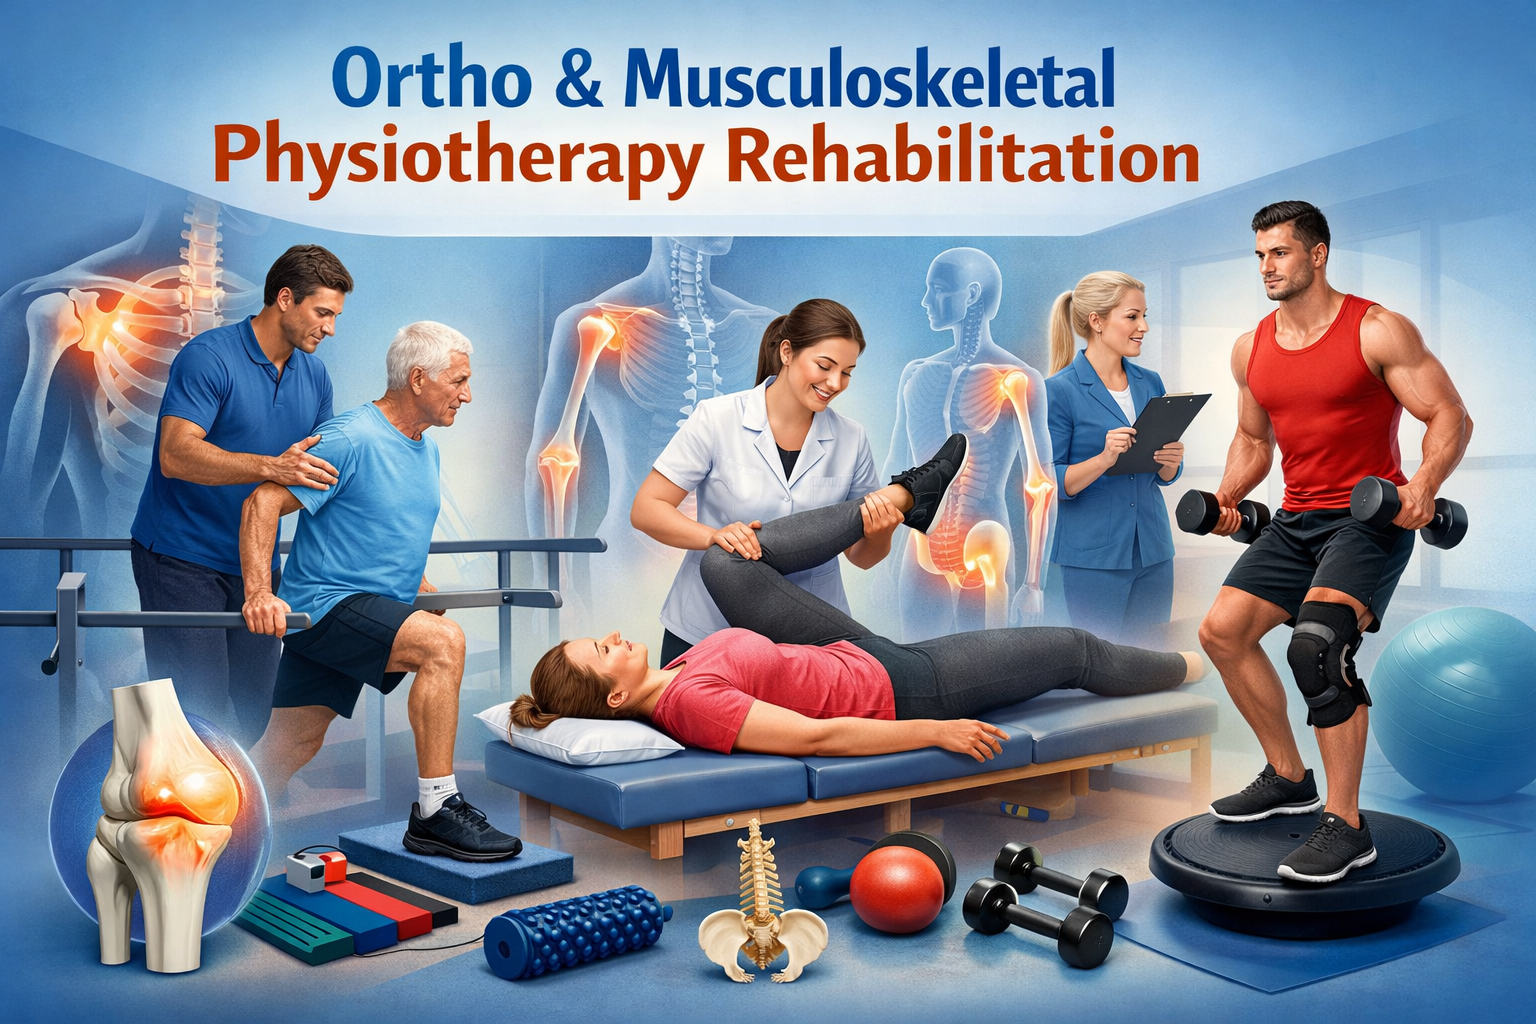

Prithivi Physiotherapy & Rehabilitation provides professional physiotherapy care for pain relief, injury recovery, and functional rehabilitation. Our goal is to help patients regain mobility, strength, and independence through evidence-based physiotherapy treatments and personalized rehabilitation programs.

✅ Evidence-Based Treatment

✅ Modern Physiotherapy Technique